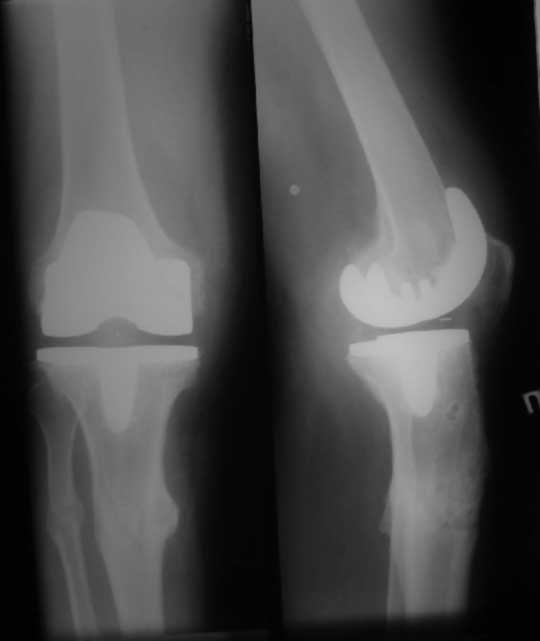

Уважаемые коллеги. Пациент 8 мес после операции ТКА, в анамнезе – неправильно сросшийся перелом голени, коррекция оси (снимки прилагаются. В настоящее время имеется разгибательная контрактура 10/5/0, на операционном столе было 90/0/5, на момент выписки движения 50/0/0 в надежде на дальнейшую разработку. До эндопротезирования 40/10/0. Глубокая инфекция исключена. Ротация бедренного компонента в норме (по КТ).

Вопросы: насколько для такого ограничения критична некорректная установка б/б компонента (я намерял 7 град)? Причина нынешнего состояния, артрофиброз? Какие действия следует предпринять, удаление рубцов, релиз головок 4-главой мышцы? Что-либо другое, ваше мнение?